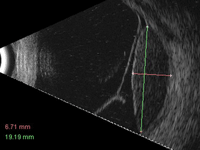

Figura 2. Tras el vacío ecogénico producido por el vítreo se observa un primer pico de reflectividad correspondiente al tumor, que de manera marcada disminuye progresivamente a medida que las ondas atraviesan la lesión, formando el denominado ángulo kappa (línea oblicua).